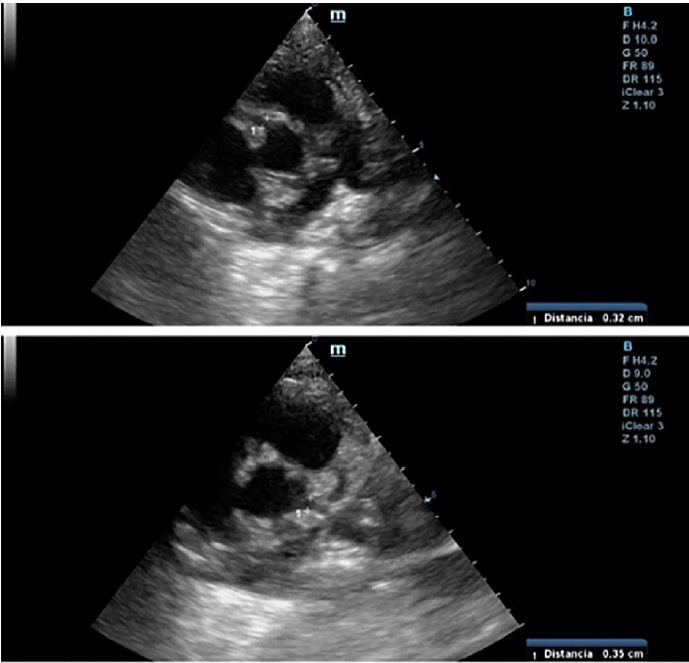

A las 24 horas del alta presenta registro febril, regular estado general, acompañado de lengua aframbuesada, edema bipalpebral y conjuntivitis. Se interna. Por laboratorio se constatan parámetros de inflamación, IgG para SARS-CoV 2 positivo y al repetir ecocardiograma Doppler (Figura 1) presenta dilatación aneurismática de ambas coronarias con función ventricular conservada (Tabla 1, se detallan los valores de las coronarias con sus respectivos Z score, en los sucesivos controles ecocardiográficos). Se reasume el cuadro como SIM-C. Recibe tratamiento inmunomediado y antiagregante plaquetario con gammaglobulina (2 gr/kg/dosis), metilprednisolona (10 mg/kg/dosis, 3 pulsos), AAS 5 mg/kg/día. Presenta leve mejoría clínica y analítica. El control cardiológico a los 5 días revela similares características. Se lo clasifica como resistente al tratamiento y se indica Infliximab (5 mg/kg). Evoluciona favorablemente, con marcada mejoría clínica y cardiovascular; se otorga el alta luego de 16 días. Se programa control cardiológico y reumatológico más tratamiento antiagregante y antiinflamatorio.

Fig. 1 Ecocardiograma Doppler 2D (eje corto de los vasos): se observa coronaria derecha en la parte superior, y coronaria izquierda en la inferior.